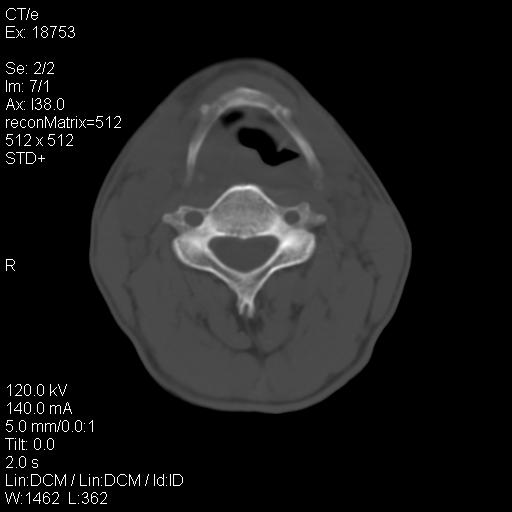

标题: CT21693:男 58岁 右侧咽部疼她2天余 PE:右侧扁桃体肿大 压痛 [打印本页]

标题: CT21693:男 58岁 右侧咽部疼她2天余 PE:右侧扁桃体肿大 压痛

1 弥漫性肿胀,与周围组织分界清晰,发病急,有明显症状,考虑急性炎症【wbc]

右化脓性扁桃体炎症伴咽后壁脓肿形成.